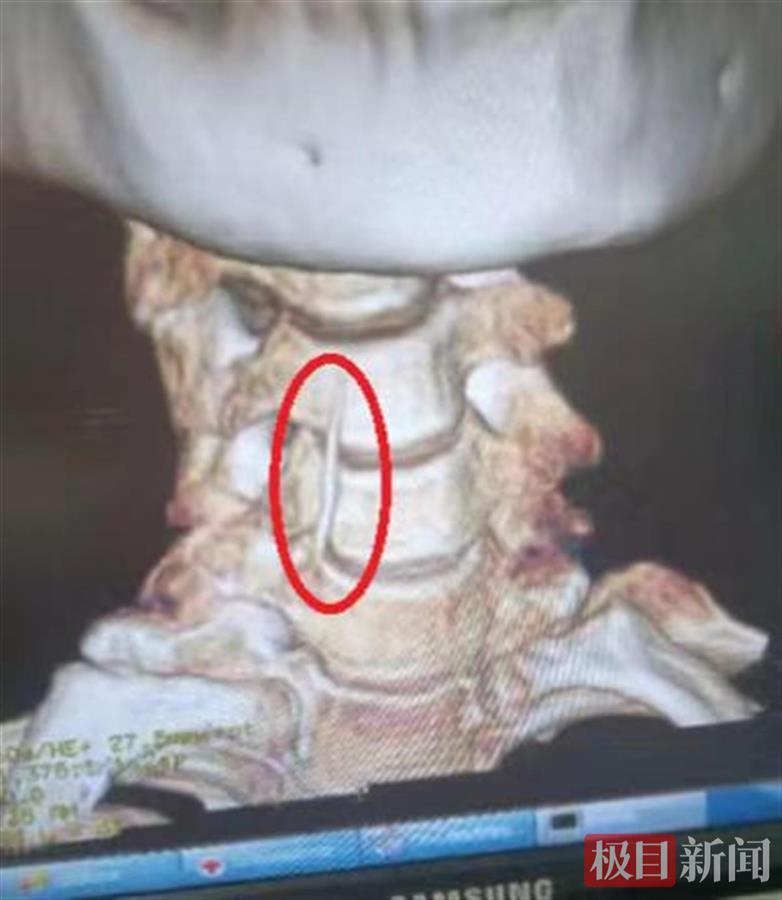

因为目视无法确定鱼刺的位置,孝感市中心医院耳鼻咽喉II病区医疗团队医护人员立即对张大娘进行CT检查,发现张大娘喉咙里的鱼刺已经穿透食道,进入颈部,一侧刺入甲状腺。

CT下显示的鱼刺 (通讯员供图)

通过CT定位鱼刺位置,医护人员在张大娘颈部将一根长3公分左右的粗大鱼刺取了出来。